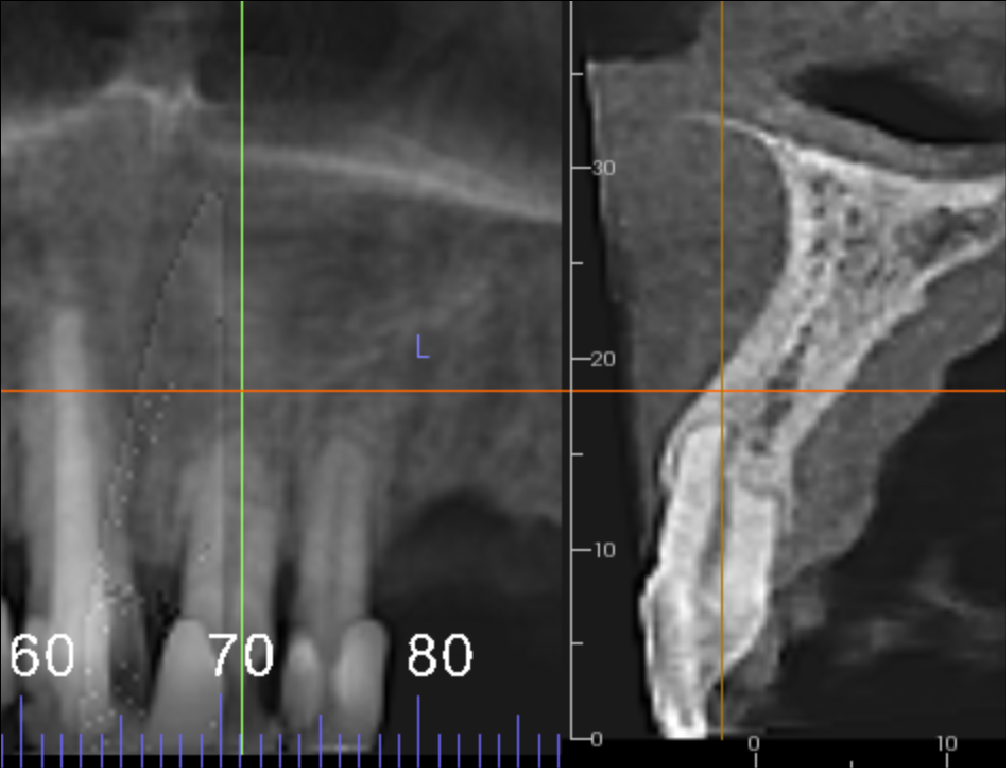

The UL1 has external root resorption, mostly on the palatal side of the root. Approximately a third to half of the root is resorbed. There is no apical radiolucency but the root may be partially ankylosed to the bone. The UL2 also has external root resorption but to a lesser extent.

UL1 showing external root resorption, mostly on the palatal side of the root. Approximately a third to half of the root resorbed. The root may be partially ankylosed to the bone